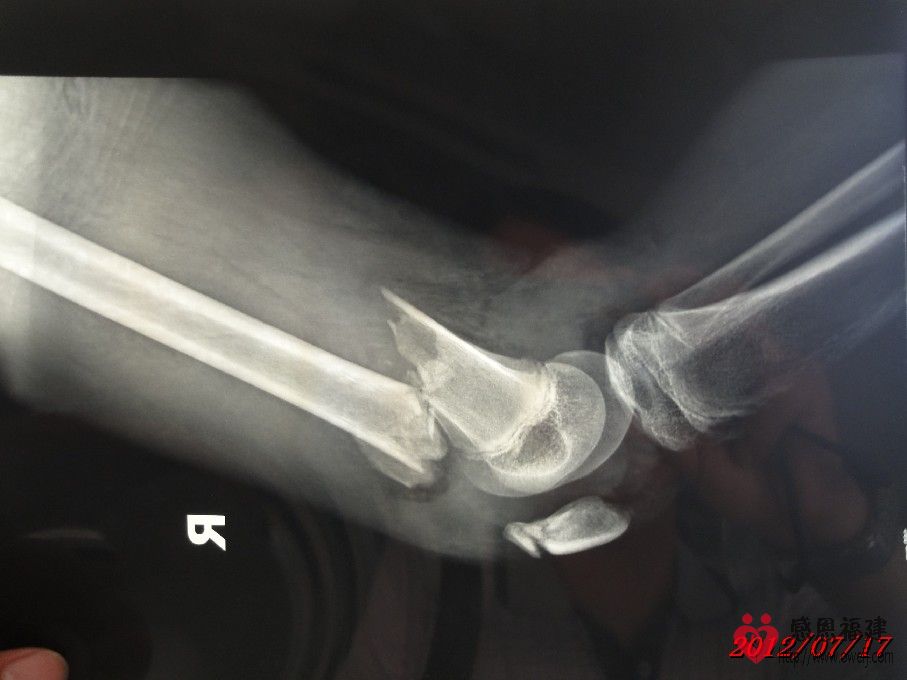

1、事故情况:2012年7月1日14:30左右,智在同学骑邻居的无牌照XGJ125摩托车载着两个同学在北洋小学附近的123县道与停在路旁的无牌照货车发生碰撞(据孩子介绍货车基本占了半边马路,当时对面刚好有车驶来,智在为了避免和对面车发生碰撞往右避让,结果撞上了停在路旁的货车的左后角),导致摩托车撞坏、智在右大腿骨折和另外一位同学大腿骨折。

2、住院情况:事故发生后家人将智在送往闽清县医院治疗,医院同意住院并可安排第二天手术;但智在是一家四口中唯一没有残疾的(由于残疾的父亲在医院照顾智在,哑巴的母亲精神不好还时常跑回老家又不会照顾人,导致眼睛残疾的小弟弟几天没吃上两顿饭),家人和亲戚为了智在治疗后不留下后遗症,最后决定送往福州市第二医院治疗,并于当晚存了2,000元住院费并办好住院手续。但由于家境贫寒,智在的父亲和亲戚到处借债(有的500,有的1,000……),好不容易东拼西凑才筹集到手术费用(现在已经累计存入医院38,000元),手术于7月11日进行,效果还比较理想,但出院时间待定。